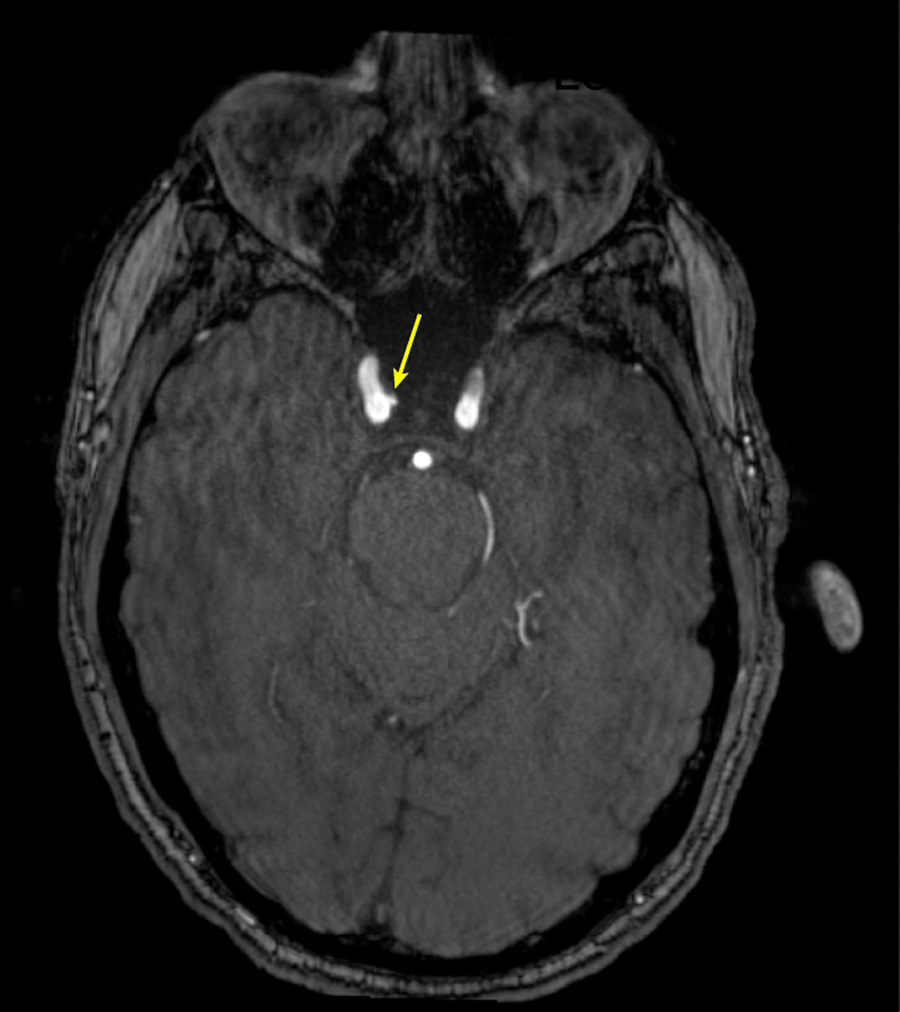

Figure 2. Representative axial time-of-flight MR angiography image in a 35-year-old male participant shows a medially projecting intracranial aneurysm (arrow) originating from the right cavernous segment of the internal carotid artery.